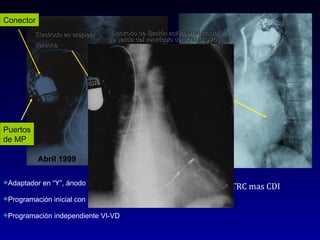

Electrodo de fijación activa en el tracto de salida del ventrículo derecho (TSVD) Abril 1999 Puertos de MP Conector Adaptador en “Y”, ánodo al TSVD y cátodo al VI. Programación inicial con retardo AV corto Programación independiente VI-VD TRC mas CDI Diciembre 2008 Electrodo en vena del seno coronario Electrodo en orejuela  derecha

Electrodo de fijaciónactiva en el tracto de salida del ventrículo derecho (TSVD) Abril 1999 Puertos de MP Conector Adaptador en “Y”, ánodo al TSVD y cátodo al VI. Programación inicial con retardo AV corto Programación independiente VI-VD TRC mas CDI Diciembre 2008 Electrodo en vena del seno coronario Electrodo en orejuela derecha